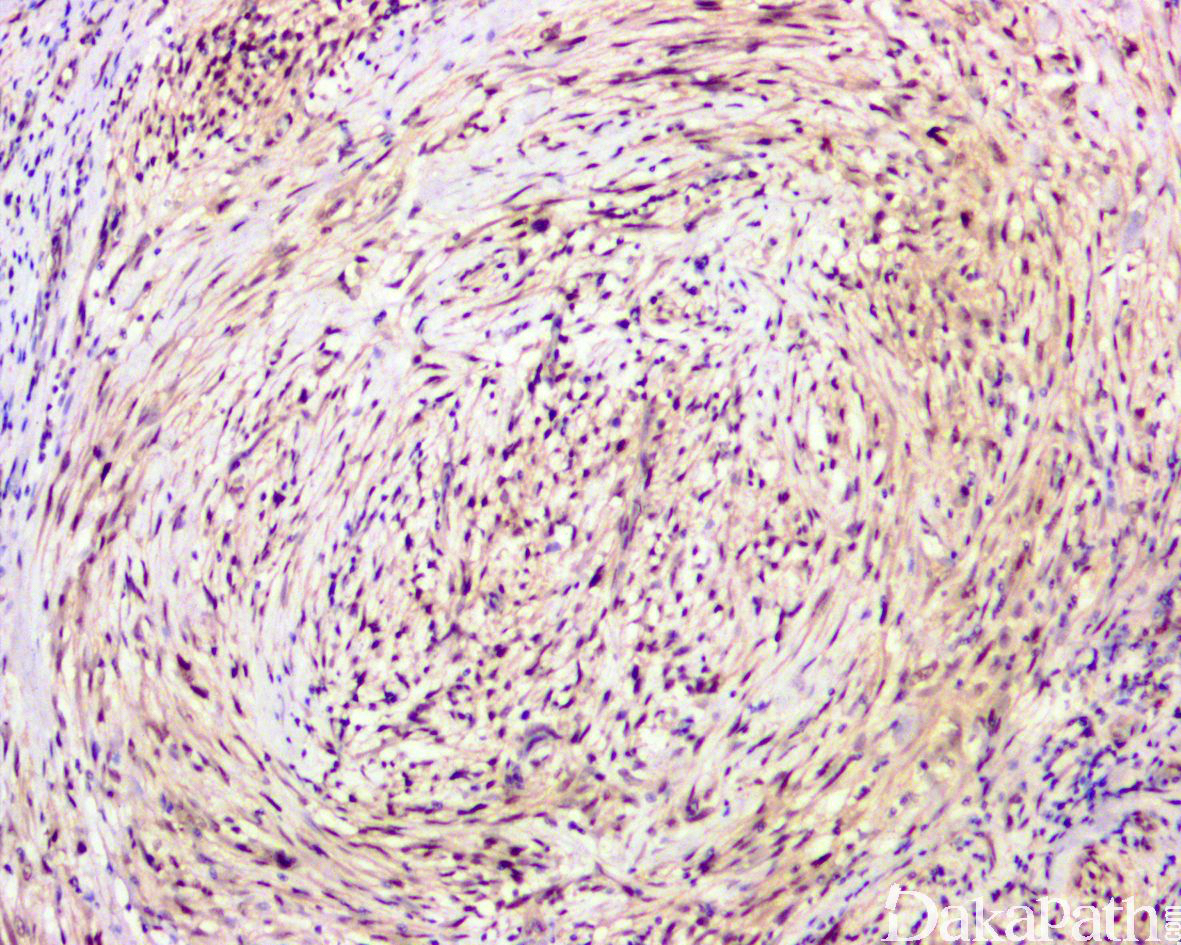

少数情况下,去分化成分可表现为低级别去分化组织学特征包括低度恶性纤维黏液肉瘤样、纤维瘤病样、炎性肌纤维母细胞瘤样以及孤立性纤维性肿瘤样等,低级别去分化成分瘤细胞以纤维母细胞样细胞为主,密度相对较低,间质较丰富,核异型性轻-中度,核分裂象< 5 个/10 HPF,罕见坏死。在后腹膜和腹部盆腔等部位的 DDLPS 可表现明显的间质黏液变性,特别是低级别 DDLPS,局部的黏液变性可导致稀疏的瘤细胞于血管周聚集从而类似于低级别黏液纤维肉瘤,而广泛的黏液变性导致局部的丛状小血管聚集和肺水肿样组织间隙使得 DDLPS 可能非常类似于黏液样脂肪肉瘤。另一少见而特殊的 DDLPS 特征为脑膜上皮样漩涡伴有化生性的骨形成,组织学上表现为低级别的梭形或胖梭形瘤细胞围绕中央小血管呈同心圆状或洋葱皮样排列,类似于脑膜瘤中常见的漩涡样结构,在漩涡的周围常见伴随的化生性骨形成。该组织学特征常出现在低级别去分化的 DDLPS 中,尽管罕见,但当其出现的时候具有高度的诊断提示作用。

免疫组织化学染色,绝大多数的 DDLPS 弥漫强表达 p16 蛋白(核和质表达),是诊断 DDLPS 最敏感的标志物,但缺乏特异性,许多与之形态学相似的肿瘤,特别是高级别肿瘤(如平滑肌肉瘤和肉瘤样癌等)亦可弥漫表达 p16。由于 DDLPS 一致性的存在 12q14-15 区域的扩增和过表达,而 MDM2 蛋白和 CDK4 蛋白的强表达与相应的基因扩增存在高度的一致性,因此免疫组织化学染色 MDM2 和 CDK4 的共表达(均为弥漫核表达)对于诊断 DDLPS 具有较大的帮助。在与 ALT/WDLPS 之外的其他类型的脂肪源性肿瘤的鉴别诊断中,联合应用 p16. MDM2 和 CDK4 对于诊断 DDLPS 具有高度的敏感性和特异性,93%的 DDLPS 表达上述 3 个标志物中的至少 2 个,72%表达全部 3 个标志物。但在 DDLPS 与非脂肪源性的肿瘤鉴别诊断时,上述 3 个标志物的特异性则明显不够;此时,应用荧光原位杂交(FISH)检测 MDM2 基因的扩增对于诊断 DDLPS(在适当的组织学背景下)具有高度的特异性和敏感性,尤其是在小活检标本、未见典型的 ALT/WDLPS 成分、低级别去分化和少见特殊类型的 DDLPS 诊断时更是如此。MDM2 基因的扩增目前普遍认为是诊断 ALT/WDLPS 和 DDLPS 的金标准,需要指出的是,MDM2 基因扩增并非 ALT/WDLPS 和 DDLPS 所特有,其他常见存在 MDM2 基因扩增的肿瘤还包括低级别中央型骨肉瘤、骨旁骨肉瘤以及原发的心脏内膜肉瘤等。约半数左右的 DDLPS 可局灶或弥漫表达 CD34,去分化成分一般不表达 S100 蛋白,伴有肌纤维母细胞分化者可表达 SMA 和 MSA 或结蛋白[23],伴有横纹肌和平滑肌分化者可分别表达 MyoD1 和 H-caldesmon,具有脑膜上皮瘤样漩涡特征的 DDLPS 可表达 SMA 和 Claudin-1 提示其肌纤维母细胞或神经束膜分化的特征。新近发现,约 6%的 DDLPS 可见 H3k27me3 的表达缺失易与恶性外周神经鞘膜瘤(MPNST)混淆,约 11%的 DDLPS 可见 STAT6 基因扩增从而局灶或弥漫表达 STAT6 易误诊为孤立性纤维性肿瘤(SFT)。